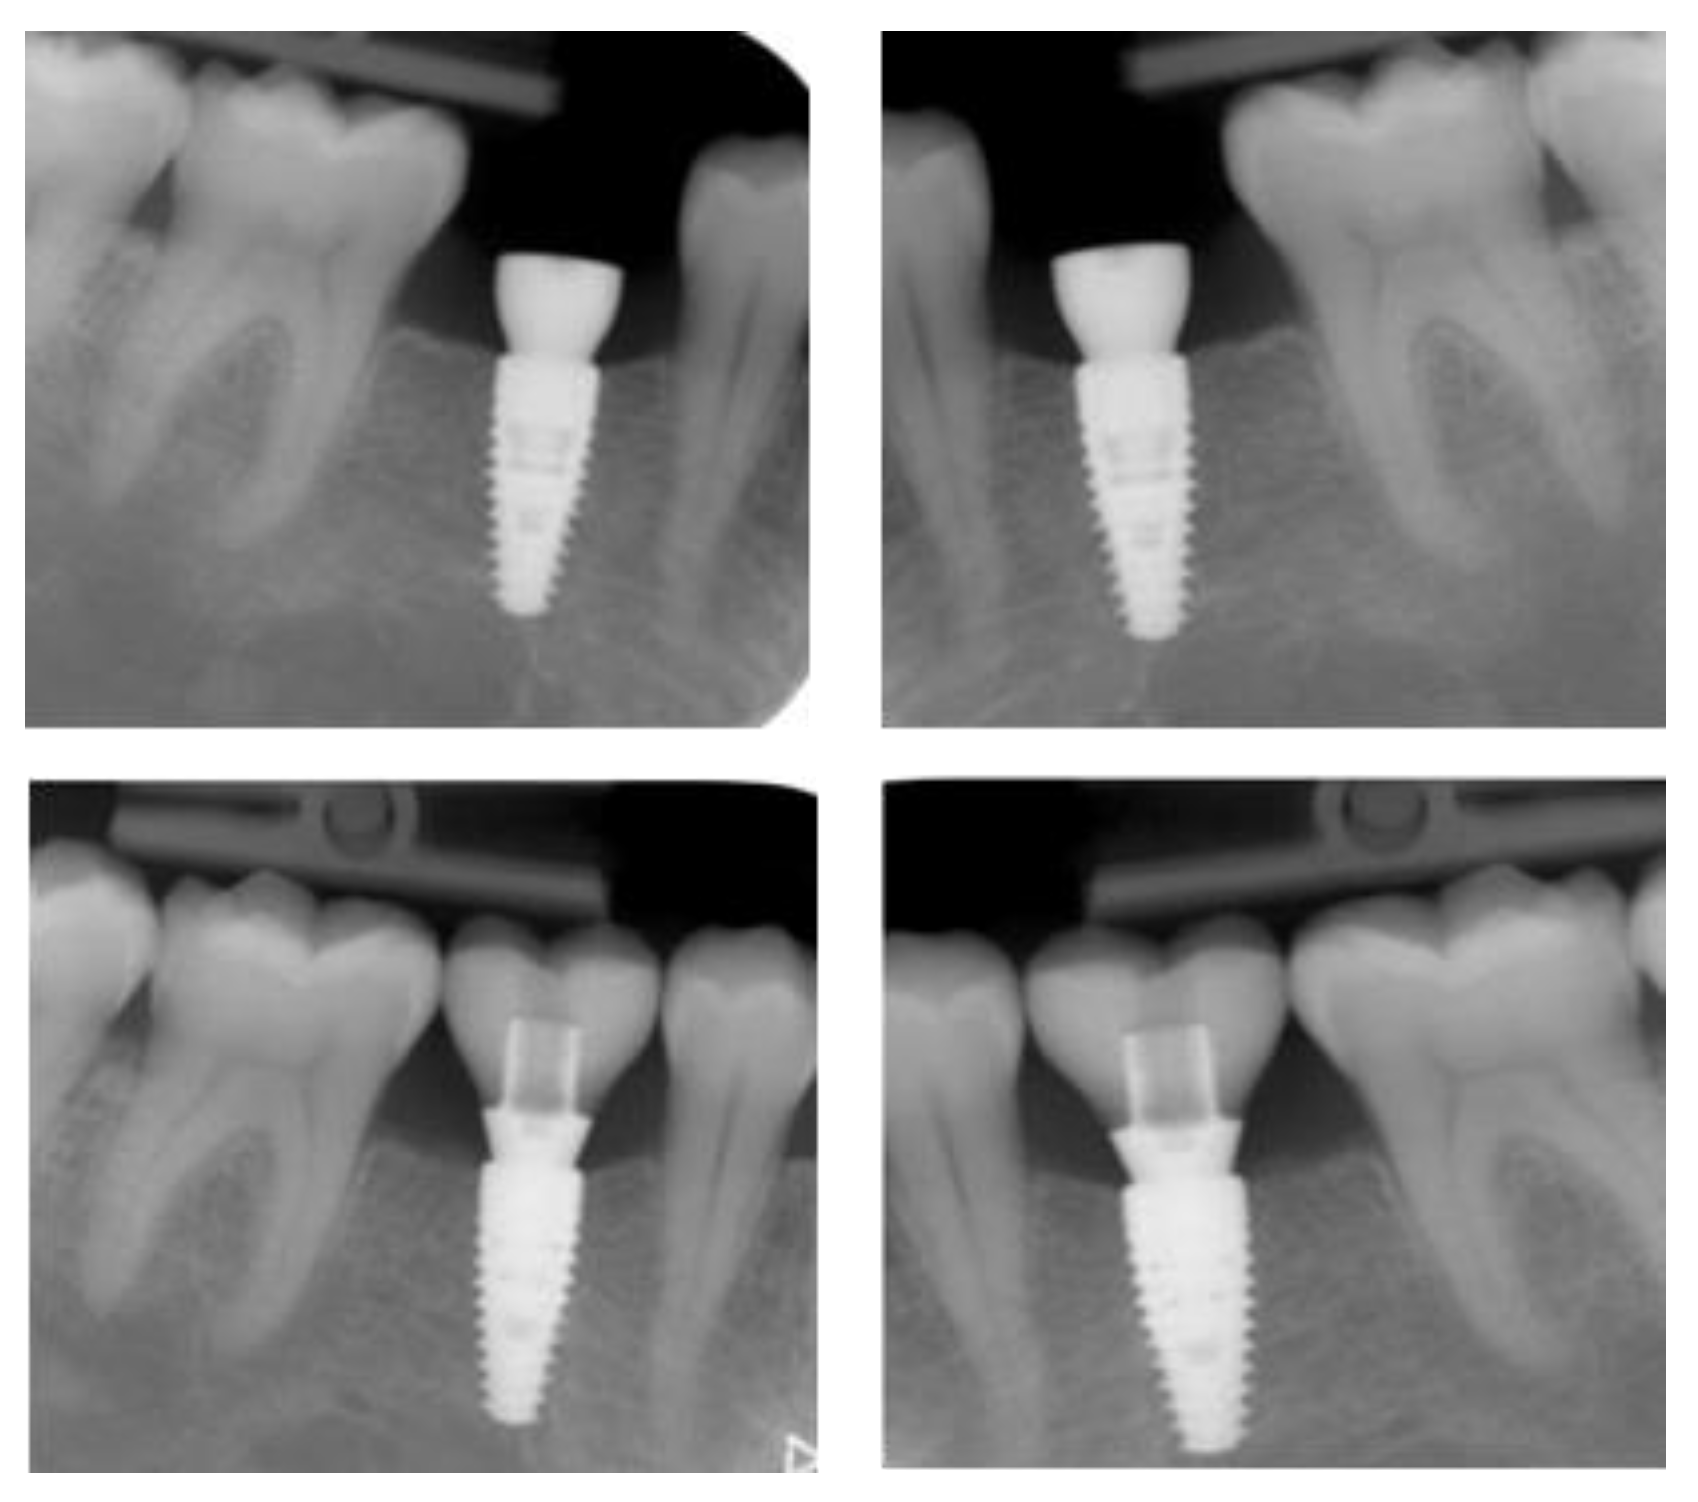

2.5. Individual Cases Description

- Case 1:

- Case 2:

- Case 3:

- Case 4:

- Case 5:

3.1. Clinical Results

3.2. Marginal Bone Level Outcomes